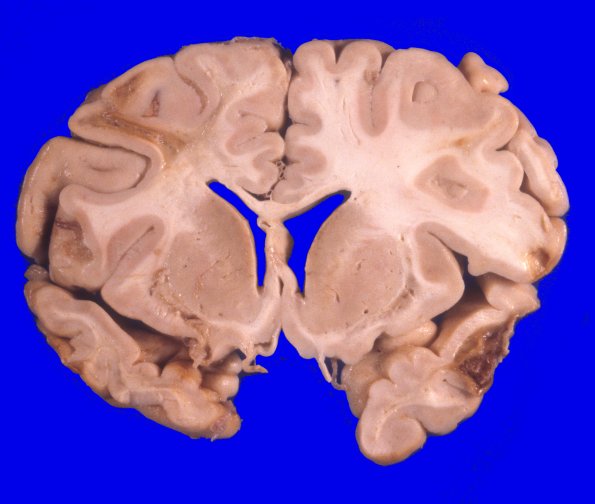

17A6 Trauma, Baseball bat (Case 17) 5

Multiple coronal sections demonstrating many severe contusive injuries with underlying loss of white matter.